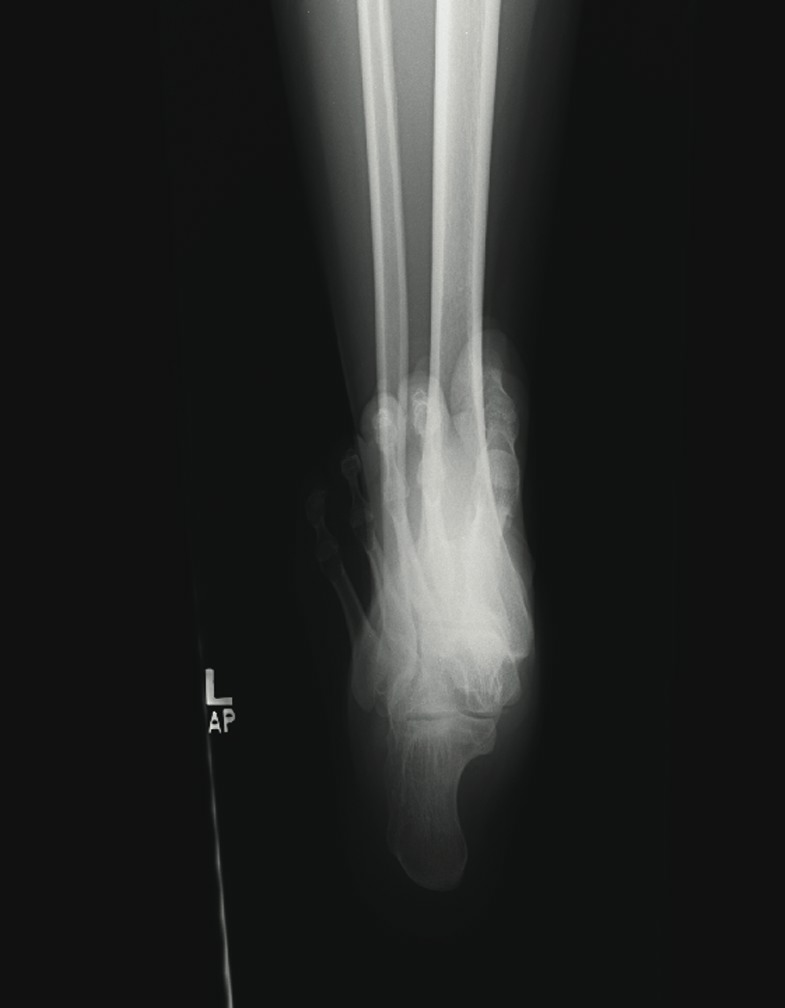

Adult-acquired flatfoot (AAF) is one of the more common conditions that podiatrists see in practice. With this in mind, some of the leading experts on this subject shared their views and experience on this subject. They discuss the role of diagnostic imaging, their use of conservative treatments and their perspectives on appropriate surgical procedures. Without further delay, here is what they had to say. Q: What ancillary studies are required for proper diagnosis and treatment selection for the adult-acquired flatfoot? A: Michael S. Lee, DPM, says AAF is generally a clinical diagnosis. Other than the physical exam, Shannon Rush, DPM, says a proper radiographic evaluation is the most important aspect of diagnosing AAF and arriving at an appropriate course of treatment. Dr. Rush emphasizes the inclusion of foot and ankle views as well as hindfoot alignment and long leg calcaneal views. All the panelists agree that neutral position X-rays are helpful in determining the degree of the deformity and what procedure one should perform. Alan Catanzariti, DPM, says it is important to evaluate the talus-first metatarsal angle on both AP and lateral radiographs. He adds that the AP views also enable one to see the amount of talar head that is covered by the navicular. Standard radiographs also allow clinicians to assess the tritarsal complex for degenerative changes, according to Dr. Catanzariti. He says these degenerative changes may indicate an arthrodesis procedure as opposed to performing reconstructive osteotomies or soft tissue procedures. The majority of the panelists recommend obtaining ankle X-rays in order to detect valgus deformity within the ankle. When there is valgus deformity within the ankle joint, Dr. Catanzariti will typically consider performing a medial displacement osteotomy of the calcaneus. “This helps decrease the tension within the deltoid ligament and prevent further attenuation of medial soft tissue structures,” explains Dr. Catanzariti. In cases of end-stage flatfoot deformity, Jordan Grossman, DPM, says AP ankle views are useful in evaluating for deltoid ligament insufficiency and valgus deformity of the talus within the ankle mortise. Gerard V. Yu, DPM, and Dr. Catanzariti agree with Dr. Rush about the value of obtaining long leg axial films. Dr. Catanzariti says long leg axial views and Saltzman views allow one to evaluate the calcaneus, subtalar joint, ankle joint and tibia relative to one another. He adds that these views often facilitate appropriate procedure selection. Lower-extremity alignment views may also be indicated in certain instances, according to Dr. Rush. Dr. Grossman concurs, noting that obtaining Cobey and hindfoot alignment views are useful in severe cases and with lower-extremity deformity. When it comes to magnetic resonance imaging (MRI), Dr. Rush says he “rarely, if ever” uses it in his workup for AAF. Dr. Catanzariti agrees. However, if he is contemplating arthrodesis versus reconstruction, Dr. Catanzariti will sometimes obtain a MRI in order to detect early degenerative changes within the subtalar joint that are subtle on standard X-rays. Dr. Grossman concurs, noting that MRI is indicated in “select circumstances” in which the diagnosis is unclear. Dr. Lee says one may employ MRI or ultrasound imaging to evaluate the posterior tibial tendon for attenuation or complete rupture. Dr. Yu emphasizes that MRI is most helpful when clinicians use a facility that has an experienced musculoskeletal radiologist, who is knowledgeable about the clinical entity and its primary and secondary manifestations. “I believe the MRI should be part of the standard workup for AAF if you plan to do direct surgical repair alone or as part of the correction of the deformity,” maintains Dr. Yu. Dr. Lee adds that a CT scan may have limited use in determining the degree of arthrosis in stage 3 or stage 4 deformities. Gait analysis may also be helpful in procedure selection, according to Dr. Catanzariti. Q: What is the significance of the posterior tibial tendon in the adult-acquired flatfoot? A: Dr. Yu says the primary purpose of the posterior tibial tendon is decelerating internal rotation of the tibia and accordingly limiting pronation of the foot following heel strike in gait. The intrinsic pathology specific to the posterior tibial tendon is “insignificant once the deformity has occurred,” notes Dr. Rush. He says the most important overriding factor is that the tendon has functionally weakened and is unable to stabilize the midtarsal joint. Dr. Rush says this functional weakness may be due to posterior tibial tendon dysfunction (PTTD) or subluxation in the rearfoot. The posterior tibial tendon plays “a primary role in the development of AAF,” according to Dr. Grossman. Dr. Lee says the posterior tibial tendon plays an important role early in the process but its importance diminishes as the deformity progresses. He notes the spring ligament may become attenuated in some situations. While there are several possible causes of AAF, Dr. Grossman says insufficiency or rupture of the posterior tibial tendon is the most common cause. The posterior tibial tendon often may be attenuated or diseased in AAF, according to Dr. Catanzariti, but he says this can vary from patient to patient. If patients have significant symptoms as a direct result of disease within the posterior tibial tendon, Dr. Catanzariti says they may require surgical intervention, which could include a tenosynovectomy, a partial tendon debridement or actual resection of an attenuated tendon. He notes these interventions may be supported by tendon transfers. In these cases, Dr. Catanzariti prefers a flexor digitorum longus tendon transfer. Dr. Rush says the clinical view of the posterior tibial tendon or its appearance on MRI does not influence one particular reconstruction over another. When it comes to stage 3 and stage 4 AAF, Dr. Lee says the posterior tibial tendon plays little importance in function, diagnosis or surgical treatment selection. If a patient has a predisposition to excessive pronation due to a specific foot structure, Dr. Yu says the posterior tibial tendon is “very significant.” When patients have a cavus foot, he notes the inherent stability of the foot will limit pronation. However, if a patient has hypermobile joint laxity syndrome, Dr. Yu says the posterior tibial tendon will be more important as it will “work harder to prevent excessive pronation.” If one stabilizes the foot well with osseous procedures, especially fusions, the importance of the posterior tibial tendon for function decreases, according to Dr. Yu. When one performs a posterior tibial tendon transfer for other conditions (i.e., dropfoot deformity), Dr. Yu says the foot structure remains the same due to the inherent interlocking of osseous units. When performing a triple arthrodesis, Dr. Yu notes the surgeon can leave the PT tendon alone altogether unless the pain there is due to active inflammation around the tendon itself. In essence, the more inherently stable the foot is, whether by surgical fusion or anatomical stability, the less important the PT tendon is to overall foot function. Q: What conservative measures have been successful in your hands in the treatment of AAF? A: Employing orthotics in combination with antiinflammatory medications and posterior muscle group stretching provides relief in milder cases of AAF, according to Dr. Catanzariti. When it comes to stage 1 conditions, Dr. Lee notes he has had a fair amount of success utilizing figure-of-eight ankle braces along with rest, ice, NSAIDs and shoe gear modifications. He notes that stage 2 deformities have responded well to prefabricated and custom orthotics, rest, activity modification and NSAIDs. Dr. Lee has also utilized ankle foot orthoses (AFOs). Depending on the presentation and degree of the deformity, Dr. Grossman says he has had success with the aforementioned modalities as well as physical therapy, cast immobilization and a removable walking boot. Functional orthotics may be helpful in the early stage of AAF but Dr. Yu says he generally does not use them. Dr. Yu notes that some companies make a variety of orthotic devices that “are too flimsy and do not have enough substance to do the job.” Essentially, one needs to ensure bracing of the foot to the leg, according to Dr. Yu, especially in the presence of other factors like obesity, genu valgum, etc. Dr. Yu says Aircast ankle braces and similar devices may provide good relief prior to using the more sophisticated and expensive devices like the Richie Brace and AFOs. With chronic conditions, Dr. Rush will use aggressive custom orthoses, Richie Braces and the Arizona AFO prior to surgical intervention. With stage 3 and stage 4 deformities, Dr. Lee will brace them with either UCBL orthotics or AFOs. If these fail, he proceeds to surgical intervention. The other panelists concur that one can use conservative bracing for stage 3 and stage 4 deformities in patients who are not surgical candidates. In these patients, Dr. Rush has had success with the Arizona AFO while Dr. Catanzariti has utilized supramalleolar AFOs with good results. In regard to conservative therapy, Drs. Rush and Yu say there are many factors to consider including the patient’s level of activity, weight loss, patient education, proper shoe gear and rehabilitation. Realistic expectations are essential and become more important as patients progress from stages 1 to 4, according to Dr. Yu. He says a patient with stage 3 or 4 deformity and low activity may respond surprisingly well to bracing but bracing is unlikely to be successful in a highly active patient with stage 2 AAF. Q: At what point does AAF become a surgical foot? A: The majority of the panelists consider surgical treatment when the deformity is progressive, grossly unstable and doesn’t respond to functional bracing. Dr. Rush says the potential progression of the deformity is a significant concern. “Severe talonavicular and subtalar subluxation can have a devastating influence on the ankle joint,” emphasizes Dr. Rush. “If the lateral peritalar drift is left unabated, the ankle can also fall into valgus.” Dr. Lee says he performs surgery for end-stage deformities such as stage 3 and stage 4 conditions. However, Dr. Yu notes that even severe deformities do not justify surgery alone. “If the other foot is flat and asyptomatic, you may be able to manage the pathologic foot without surgery,” points out Dr. Yu. If bracing fails, one needs to turn to surgical options, according to Dr. Yu. He emphasizes that physicians should always remember to treat patients in conjunction with their disease or deformity and not the X-rays. He notes that clinical correlation is essential to effective treatment. Q: When are calcaneal osteotomies indicated in the treatment of AAF? A: Dr. Yu says these procedures are “rarely” indicated for treating AAF. He believes this approach has been abused in an attempt to avoid more time-tested techniques, such as the gold standard triple arthrodesis, especially in the later stages of AAF when the deformity can be quite severe. In his experience, Dr. Yu says the calcaneal osteotomy has little impact in resolving severe AAF “when a fusion in conjunction with tibialis posterior repair and posterior lengthening would have worked out better.” While he notes that calcaneal osteotomies are very helpful in the earlier stages of the disease, Dr. Yu emphasizes that many of these patients will do well without surgery. Drs. Grossman, Catanzariti and Lee believe calcaneal osteotomies are primarily indicated for flexible or reducible deformities. These procedures allow surgeons to correct various deformities while maintaining midtarsal and subtalar joint motion, according to Dr. Grossman. He says this will “most likely decrease the likelihood of adjacent joint demand and arthrosis that one commonly sees with an isolated or triple arthrodesis.” Citing the versatility of calcaneal osteotomies, Dr. Catanzariti calls them an excellent alternative to arthrodesis procedures. “These osteotomies spare the tritarsal complex and allow the hindfoot to function in a relatively normal fashion,” explains Dr. Catanzariti. Dr. Lee concurs. If the flatfoot is supple, he says one can achieve correction with calcaneal osteotomies while preserving most of the hindfoot motion. When it comes to late stage 1 AAF, Dr. Catanzariti will consider posterior calcaneal displacement osteotomies and sometimes uses this approach to treat early stage 2 conditions. Dr. Lee utilizes posterior calcaneal displacement osteotomies for early stage 2 AAF and employs the Evans calcaneal osteotomy and double osteotomies for late stage 2 conditions. For mid- to late stage 2 AAF, Dr. Catanzariti considers performing an anterior open wedge osteotomy in combination with a posterior displacement osteotomy. Dr. Rush says calcaneal osteotomies are a “wonderful surgical tool” for treating AAF. He performs a posterior osteotomy with any valgus malalignment of the subtalar joint when a subtalar arthrodesis is not indicated. Obtaining hindfoot alignment and long leg calcaneal axial views help in planning with this procedure, according to Dr. Rush. He maintains that clinicians must be careful to evaluate the midtarsal joint and medial column for instability and supinatus. In the presence of instability or deformity, Dr. Rush notes one must add ancillary procedures in order to stabilize the medial column. Dr. Rush adds that naviculocuneiform arthrodeses serve to stabilize the medial column and address the naviculocuneiform fault if one exists. Dr. Grossman says he typically performs calcaneal osteotomies in combination with other bony and/or soft tissue procedures. Dr. Rush does not utilize an isolated anterior calcaneal osteotomy for AAF. He says one must combine this procedure with the posterior osteotomy to correct the valgus and lateral translation in the subtalar joint. Dr. Rush strongly emphasizes paying close attention to the subtalar alignment when selecting these procedures. Dr. Lee also notes that he prefers calcaneal osteotomies over isolated hindfoot fusions when treating AAF in smokers, more active patients and those with a normal or slightly elevated body mass index (BMI). Q: When is an isolated or combined joint arthrodesis indicated in treating AAF? A: According to Dr. Yu, these procedures are indicated when there is significant deformity with significant disability and symptoms, especially in cases that involve degenerative arthritis or excessive mobility that cannot be predictably controlled by other means. When one considers performing three joint preservation procedures, Dr. Yu believes one joint fusion can achieve the same outcome. He says performing an isolated joint fusion is especially beneficial for patients who have a low level of activity and want relief of their pain and a stable foot. If one achieves the fusion in a neutral position without varus or valgus, Dr. Yu says the fusion provides “exceptional functional outcomes” with minimal stress on adjacent joints, which minimizes the risk of subsequent degenerative joint disease. “It’s all about the alignment and position of fusion,” emphasizes Dr. Yu. Over the years, Dr. Yu notes anecdotally that he has observed, examined and analyzed a large number of adult patients who had congenital coalitions, realizing they had minimal to no symptoms until their late 40s and 50s or even later. Dr. Yu says the position of the fusion is key to minimizing stress on adjacent joints and structures. Tarsal coalition patients who present early in life invariably have peroneal spastic flatfoot deformities, creating a completely different clinical problem, according to Dr. Yu. However, he emphasizes that the technique one uses to perform these fusions is important. Rigid deformities, a degenerative midtarsal or subtalar arthritis are the primary indications for using isolated or combined arthrodesis procedures, according to Dr. Grossman. He says one may also consider these procedures for obese patients with AAF or in cases of underlying inflammatory arthritis. Dr. Grossman says he typically combines an isolated arthrodesis procedure with soft tissue reconstruction and posterior muscle group lengthening. As with all arthrodesis procedures, Dr. Grossman says the position primarily predicates outcomes and patient satisfaction. Dr. Lee utilizes isolated hindfoot fusions in late stage 2 deformities when there may be mild arthrosis in one or more of the hindfoot joints, when the deformity is severe on plain radiographs or in patients with a higher BMI. A subtalar joint arthrodesis may be effective in the presence of isolated subtalar joint disease or arthritis, according to Dr. Catanzariti, but he rarely uses this procedure to treat AAF. In these cases, Dr. Catanzariti prefers a double calcaneal osteotomy for stage 2 AAF, a triple arthrodesis for stage 3 AAF and a combination of triple arthrodesis and posterior calcaneal displacement osteotomy for stage 4 AAF. On the other hand, Dr. Lee says he tends to perform an isolated subtalar joint arthrodesis in many cases of AAF but will occasionally opt for talonavicular arthrodesis in more severe cases of AAF with significant talar declination. Dr. Rush notes that painful degenerative joints and significant subluxation in the subtalar or talonavicular joints are general indications for arthrodesis. Arthrodesis of the non-essential medial column joints, such as the naviculocuneiform or metatarsocuneiform joints, can easily and effectively stabilize the medial arch, according to Dr. Rush. He adds that combining this procedure with calcaneal osteotomies can “correct most degrees of instability.” While distraction fusions are effective for lateral peritalar subluxation, Dr. Rush cautions that they often do not address the valgus or translation in the subtalar joint. According to Dr. Lee, distraction arthrodesis of the calcaneocuboid joint is a powerful procedure but does have “some elevated risk of non-union.” In the presence of supinatus or varus deformities, all the panelists agree that one must perform some type of ancillary medial column procedure, whether it is a medial column fusion or an osteotomy. Dr. Mendicino is Chief of the Division of Foot and Ankle Surgery at the Western Pennsylvania Hospital in Pittsburgh. He is a Fellow and Past President of the American College of Foot and Ankle Surgeons, and is a Clinical Professor of Surgery at the Western Campus of the Temple University School of Medicine. Dr. Catanzariti is the Director of the Residency Training Program within the Division of Foot and Ankle Surgery at the Western Pennsylvania Hospital in Pittsburgh. He is a Fellow of the American College of Foot and Ankle Surgeons. Dr. Grossman is Chief of the Section of Podiatry at Akron General Medical Center in Ohio. He is a Fellow of the American College of Foot and Ankle Surgeons, and a Diplomate of the American Board of Podiatric Surgery. Dr. Lee is a Fellow and serves on the Board of Directors of the American College of Foot and Ankle Surgeons. He is a Diplomate of the American Board of Podiatric Surgeons. He recently chaired the adult flatfoot panel and co-authored the ACFAS Clinical Practice Guidelines for Adult Flatfoot. He is in private practice at Central Iowa Orthopedics in Des Moines, Iowa. Dr. Rush is a Fellow of the American College of Foot and Ankle Surgeons. He is a Staff Surgeon within the Department of Orthopedics at Kaiser Permanente in Walnut Creek, Ca. Dr. Rush is also a Staff Surgeon with the San Francisco Bay Area Foot and Ankle Residency Program. Dr. Yu is the Director of the Podiatric Surgical Residency Program (PSR-36) and is the Chief of the Section of Podiatry of the Division of Orthopedic Surgery at the St. Vincent Charity Hospital, and at the Huron Hospital in Cleveland. He is a Fellow of the American College of Foot and Ankle Surgeons, and is a Diplomate of the American Board of Podiatric Surgery. Dr. Yu is also the Director of Program Development and a faculty member of the Podiatry Institute.